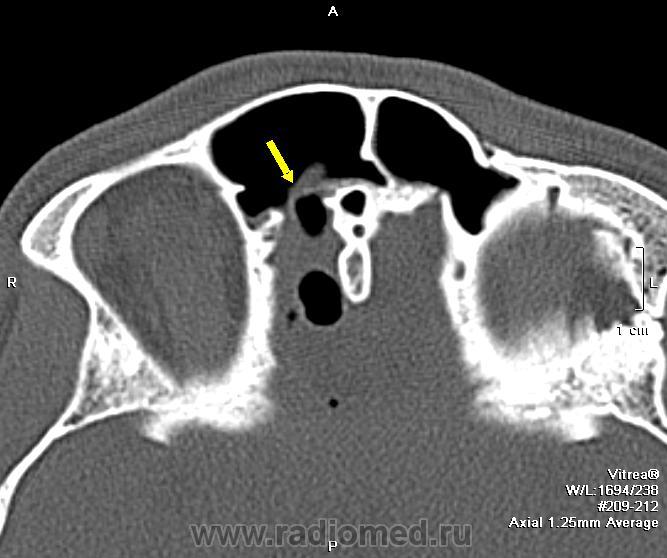

На снимках виден большой костный дефект (желтая стрелка) в задней стенке лобной пазухи, в полости черепа воздух, который прослеживается в области дефекта в полюсе лобной доли, в большой порэнцефалической кисте с уровнем жидкость-воздух (красные стрелки). Киста связана в передним рогом бокового желудочка, в противоположном желудочке и в третьем воздух (зеленые стрелки). На сагиттальных срезах виден воздух в мостовой цистерне вдоль ската. Поскольку дефект довольно большой, сейчас решается вопрос как лучше его закрыть эндоскопически или через трепанацию.